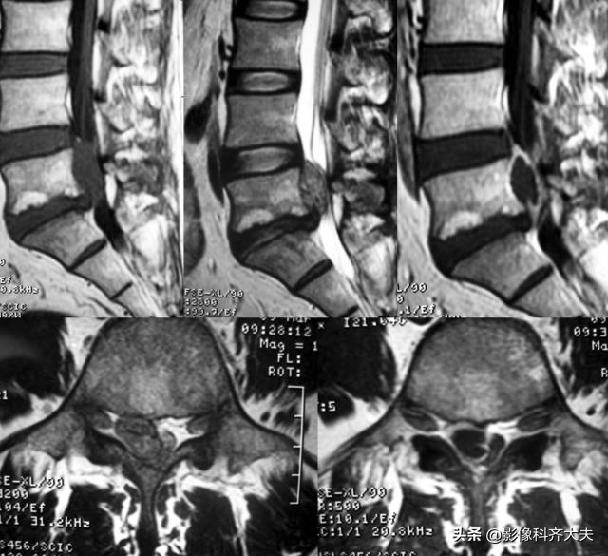

正侧位示腰4、5间隙变窄,CT扫描示腰4、5间盘突出

CT:椎间盘突出(中央型)

MRI:椎间盘突出(外侧型)